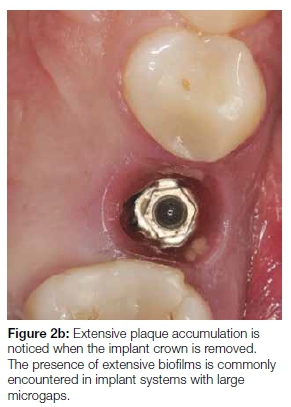

Proposed criteria of acceptable bone loss of 1.5 mm during the first year of loading, and 0.2 mm annually thereafter, are still widely accepted by the scientific community.16 Significant changes in implant treatment protocols have occurred, ranging from using machined-surfaced implants and mainly restoring the edentulous jaw, to current protocols involving surface-enhanced implants restoring single missing teeth. Many other non-infectious factors may also contribute to early bone loss. The reader is referred to a published article for a more comprehensive review on this topic.25 The amount of bone remodeling depends on implant hardware, surgical technique, prosthesis design, and patient factors.16,25 The presence or absence of a dental implant-abutment interface that may harbor bacteria plays an important role in peri-implant health. A chronic presence of inflammatory-cell infiltrate is found whenever a micro-gap is present (Figures 2a and 2b).20 Histological differences exist between periodontitis- and peri-implantitis lesions.